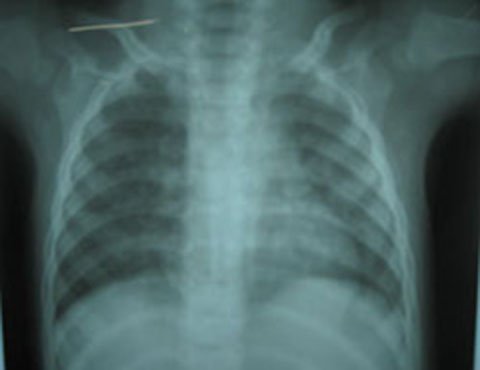

Xẹp phổi vì sặc xương heo, một bé trai suýt chết

Ăn cháo thịt heo, một bé trai 13 tháng bị mảnh xương găm vào phổi, suýt tử vong.